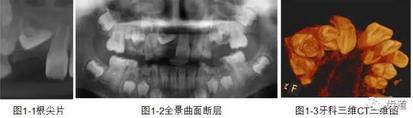

一)牙體牙髓病科

CBCT在牙體牙髓病科治療中,對牙根周圍的解剖關(guān)系、炎癥病變、囊腫等就能夠輕而易舉的進行診斷。甚至與牙齒內(nèi)根管的數(shù)目、走向、分支等都能夠通過牙科CT進行展示,使臨床醫(yī)生的根管治療不再是完全憑手感的“經(jīng)驗科學(xué)”。通過CBCT,還可以對一些“久治不愈“的疑難病例進行檢查和診斷,例如根縱列的診斷、根管內(nèi)異物的定位等,找準(zhǔn)了原因,結(jié)合先進的治療技術(shù)因病施治,使疑難病例的治療變的輕松起來。

1、牙髓根管治療

1)根管治療中牙膠尖充填在CBCT中的影像

2)根管測量

2、多生牙

多生牙的定位